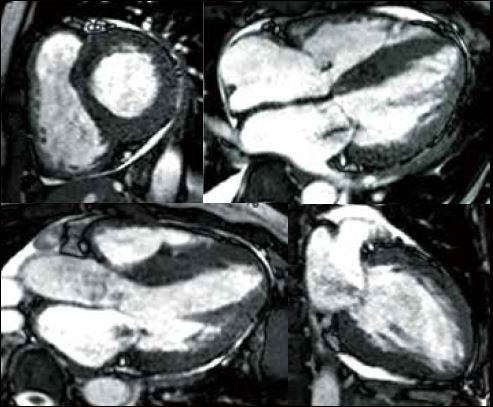

Клінічний випадок 1

Історія пацієнта

Чоловік 75 років, який 2 місяці тому хворів на стенокардію напруги. Його направили до нашого центру візуалізації для оцінки ішемічної хвороби серця.

Стрес-перфузія МРТ показала стрес-індуковані дефекти перфузії в передньоперегородці (anteroseptum) та бічній стінці, що свідчить про багатосудинне захворювання коронарної артерії, наприклад ліву передню низхідну і ліву огинаючу артерію. Пізнє посилення гадолінію (ППГ) показало невелику яскраву пляму в субендокарді базальної бічної стінки. Дрібноплямиста ППГ вказувала на нерозпізнаний субендокардіальний інфаркт міокарда. Коронарна МРА виявила зниження сигналу в лівій головній коронарній артерії, що свідчить про високий ступінь стенозу в лівій головній коронарній артерії. Машина швидкої медичної допомоги доставила потерпілого до лікарні для надання невідкладної допомоги. Під час екстреної інвазивної коронарної ангіографії було виявлено стеноз лівої головної коронарної артерії високого ступеня. Подальше черезшкірне коронарне втручання було виконано успішно без жодних ускладнень.